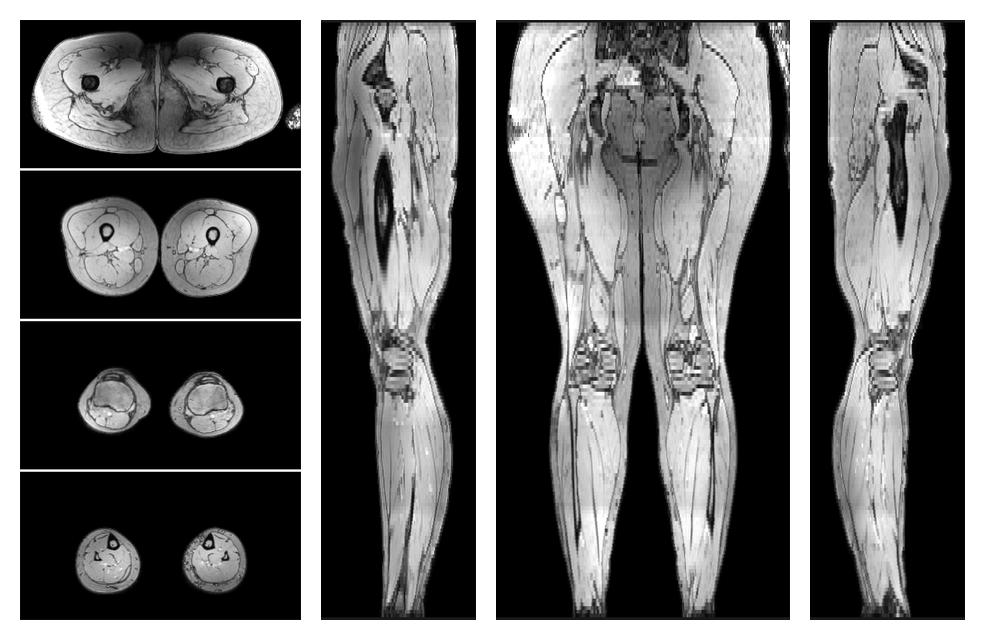

Water only T2 mapping

Multi echo spin echo T2 relaxation time mapping with EPG reconstruction, for information look here».

• Water only signal

The water part of the acquired multi-echo spin echo data.

• Water only T2 relaxation time

The water only T2 relaxation time of the lower extremity obtained from multi echo spin echo t2 mapping with EPG based reconstruction.